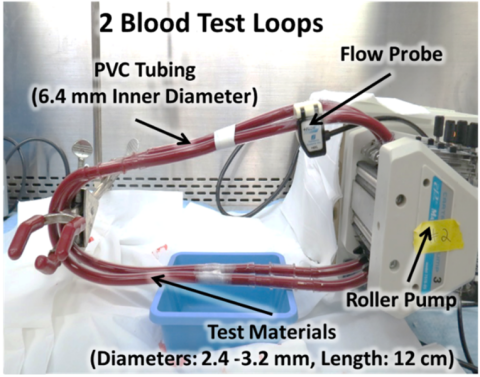

An In Vitro Blood Flow Loop System for Thrombogenicity Evaluation of Medical Devices and Biomaterials

Categories:

Lab Method

This tool provides a step-by-step protocol to design a recirculating flow loop test system and perform in vitro thrombogenicity testing of catheter-like blood-contacting medical devices and materials using blood from several animal species. The protocol also provides details about different markers for thrombogenicity testing.

Program Areas:

Cardiovascular